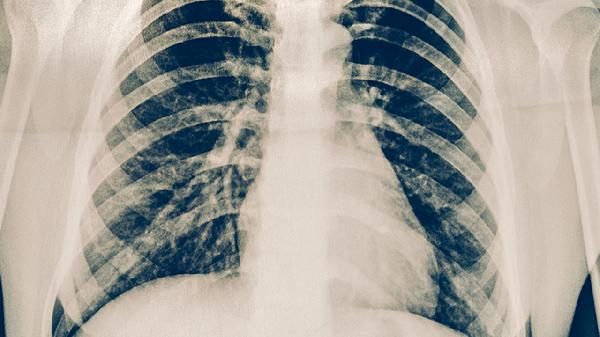

肋骨骨折患者一般可以吃大虾,但需注意过敏或胃肠不适等特殊情况。大虾富含优质蛋白和钙,有助于骨折恢复。

肋骨骨折后适量食用大虾可为身体补充修复所需的营养物质。大虾中的优质蛋白是组织修复的重要原料,钙元素则参与骨骼重建过程。烹饪时建议选择清蒸、水煮等低脂方式,避免油炸或辛辣调味,以免刺激胃肠。每日摄入量控制在100-150克为宜,可搭配蔬菜水果保证营养均衡。